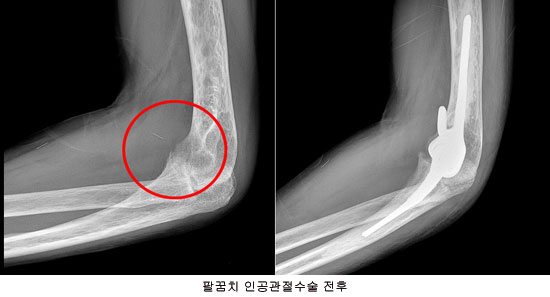

수술적 치료법인 팔꿈치 인공관절치환술은 부위마취를 한 뒤 팔꿈치에 8~10㎝정도의 최소절개를 통해 통증을 유발하는 부서진 관절연골(물렁뼈)과 뼈, 활액막 등을 제거하고 손상된 관절이 있던 자리에 골 시멘트를 이용해 새 인공관절을 부착하는 방법이다. 이때 모니터에 연결된 투시 카메라를 통해 환자의 상지 정렬 축 및 관절 면을 정확하게 계측해 불필요하게 튀어나온 팔뼈는 절단하고 변형된 팔뼈의 각도를 교정해 정상 상태의 팔 모양을 되찾을 수 있도록 한다. 새 인공관절은 지르코늄이라는 신소재로 만들어져 표면이 매끈하고 마모가 적다는 장점이 있다.